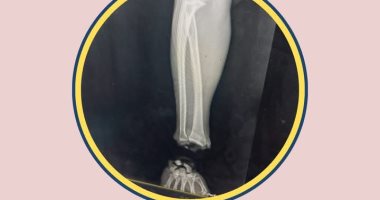

الاشعة العادية بعد التوصيل

الأشعة قبل عملية التوصيل